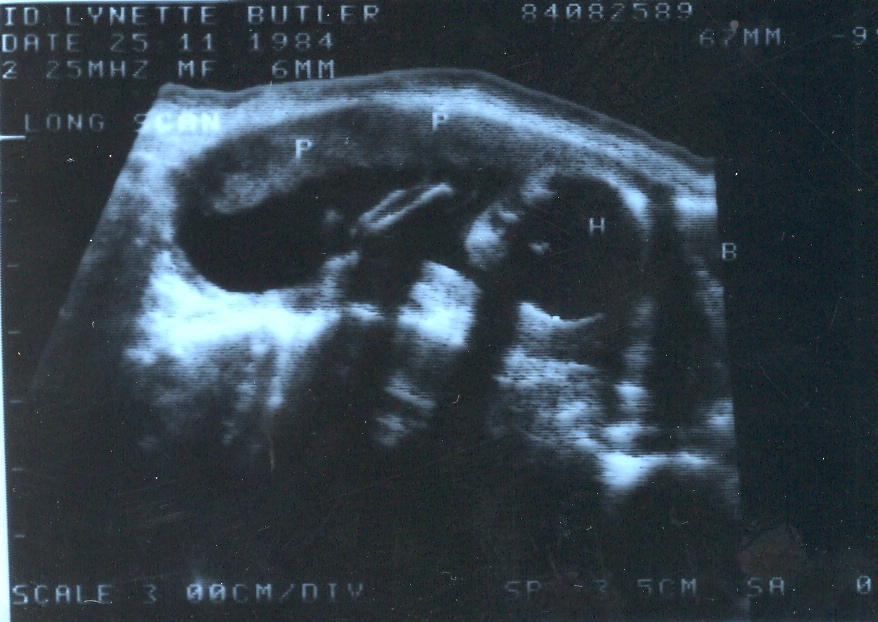

On November 25, 1984 we got our first look at the newest member of the family, but with ultrasound technology being what it was at that time and in that country, that look wasn’t a very good one.  The doctor told me that if he had to make a guess about the sex of the baby, he’d say it looked like it was a boy.  But he cautioned me against buying a lot of boy things, because it was too early (26 weeks) to be very sure

Can you even tell this is a baby?  His head is on the right side of the image.

Can you even tell this is a baby? His head is on the right side of the image - identified by the "H".